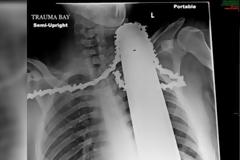

Απίστευτο: Το αλυσοπρίονο χώθηκε στον λαιμό του και... [photos]

Αυτό που βλέπετε είναι η ακτινογραφία που έκαναν οι γιατροί στον 21χρονο James Valentine, όταν αυτός εισήχθη στα επείγοντα του Γενικού Νοσοκομείου Allegheny στο Πίστμπουργκ των